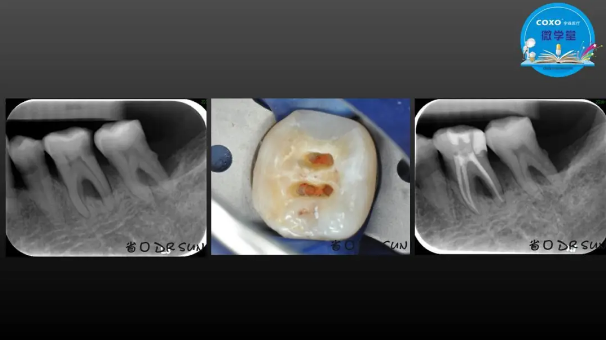

主講:孫書昱

主任醫(yī)師,牙體牙髓副主任, 廣東省口腔醫(yī)院牙體牙髓科 主任醫(yī)師。2003年碩士研究生畢業(yè),研究方向為牙體牙髓病學,擅長于牙體牙髓病的診斷、齲齒、牙髓炎、根尖周病的治療以及前牙美容修復。